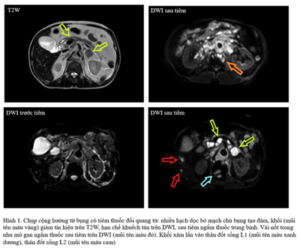

Case lâm sàng: Điều trị bệnh nhân ung thư biểu mô tế bào gan tại Trung tâm Y học hạt nhân và Ung bướu – Bệnh viện Bạch Mai

Case lâm sàng: Điều trị bệnh nhân ung thư biểu mô tế bào gan tại Trung tâm Y học hạt nhân và Ung bướu – Bệnh viện Bạch Mai GS.TS. Mai Trọng Khoa, PGS.TS. Phạm Cẩm Phương, Ths. Lê Quang Hiển, BSNT. Cao Văn Trung, BSNT. Đỗ Đăng Thọ Trung tâm...